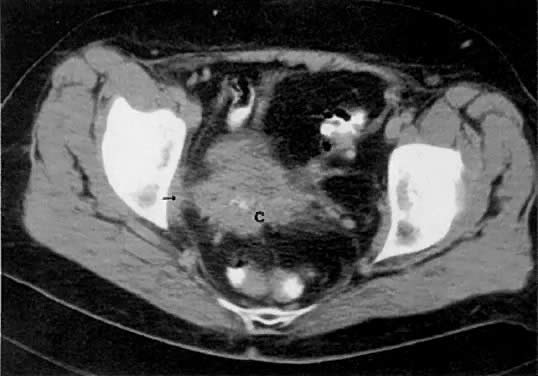

LOCAL CT STAGING.

Normal adult ovaries are not necessarily seen on CT as separate structures from the adnexae, which are generally shown as symmetric soft-tissue densities on both sides of the uterus. It may also be difficult to distinguish the ovaries from adjacent bowel loops unless these are well opacified by contrast material. The detailed internal ovarian architecture seen on ultrasound or MRI is not usually seen on CT. Mere contiguity of ovarian masses to the uterus may be difficult to differentiate from uterine invasion (see Fig. 33 and Fig. 35A). CT is more useful in detecting ascites, pelvic or mesenteric masses, large peritoneal implants, nodal involvement, and liver metastases.